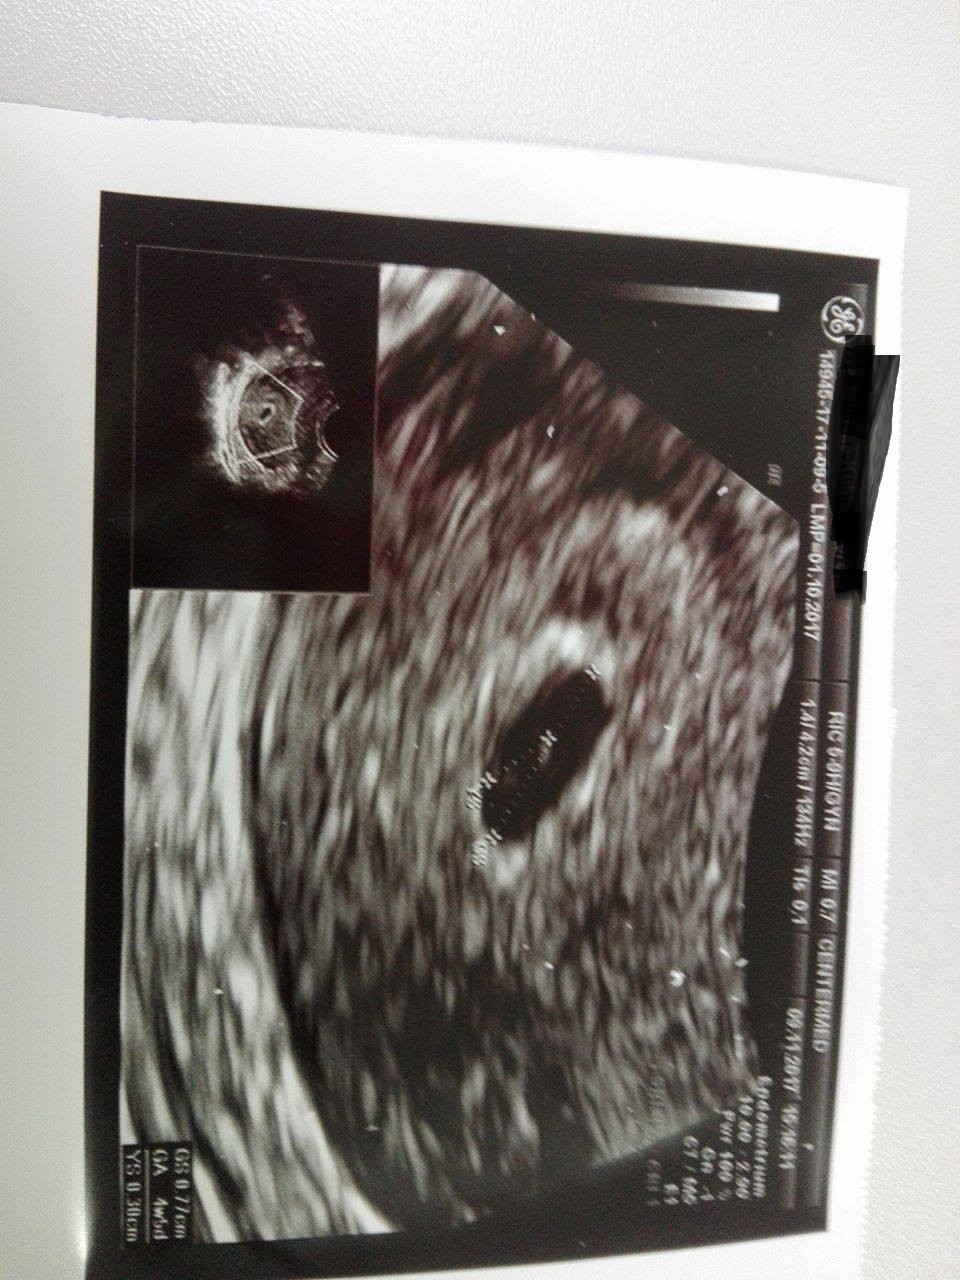

Cudeńko malutkie :* gratulujęWrzucam fotkę Kropka z wczorajW środku cień zarodka.

Wrzucam fotkę Kropka z wczorajW środku cień zarodka.